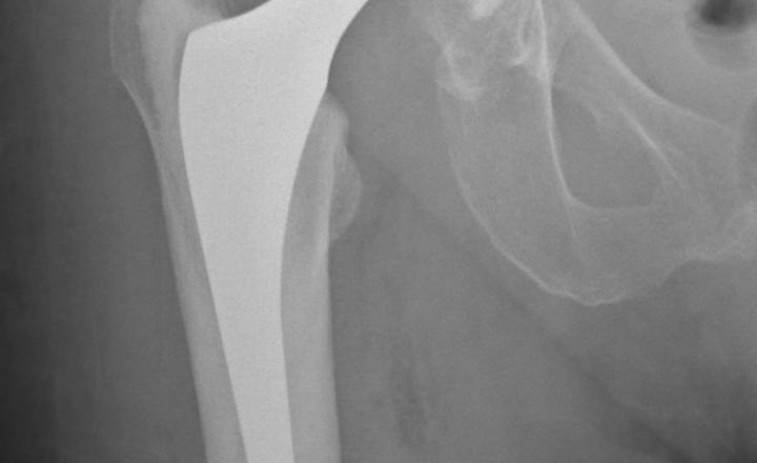

Las fracturas de cadera elevan el riesgo de mortalidad en personas mayores

La evidencia científica respalda esta preocupación.